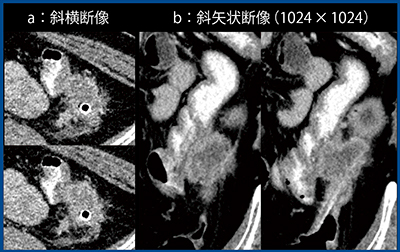

2.泌尿器科領域

症例2は複雑性腎囊胞である。従来CT(図3 a)では単純囊胞と診断される懸念もあるが,Aquilion Precision(図3 b)では小さな充実性部分が明瞭化している。治療方針の決定に重要な微小病変を描出できることは,Aquilion Precisionの強みであると考える。

図3 症例2:複雑性腎囊胞